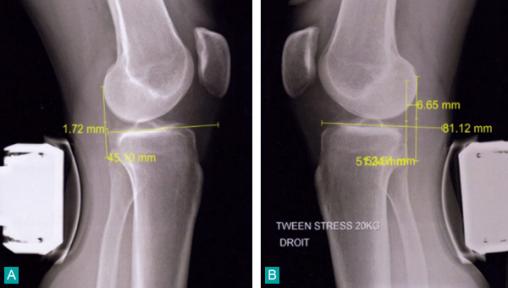

Lésion méniscale médiale traumatique verticale de grade 3